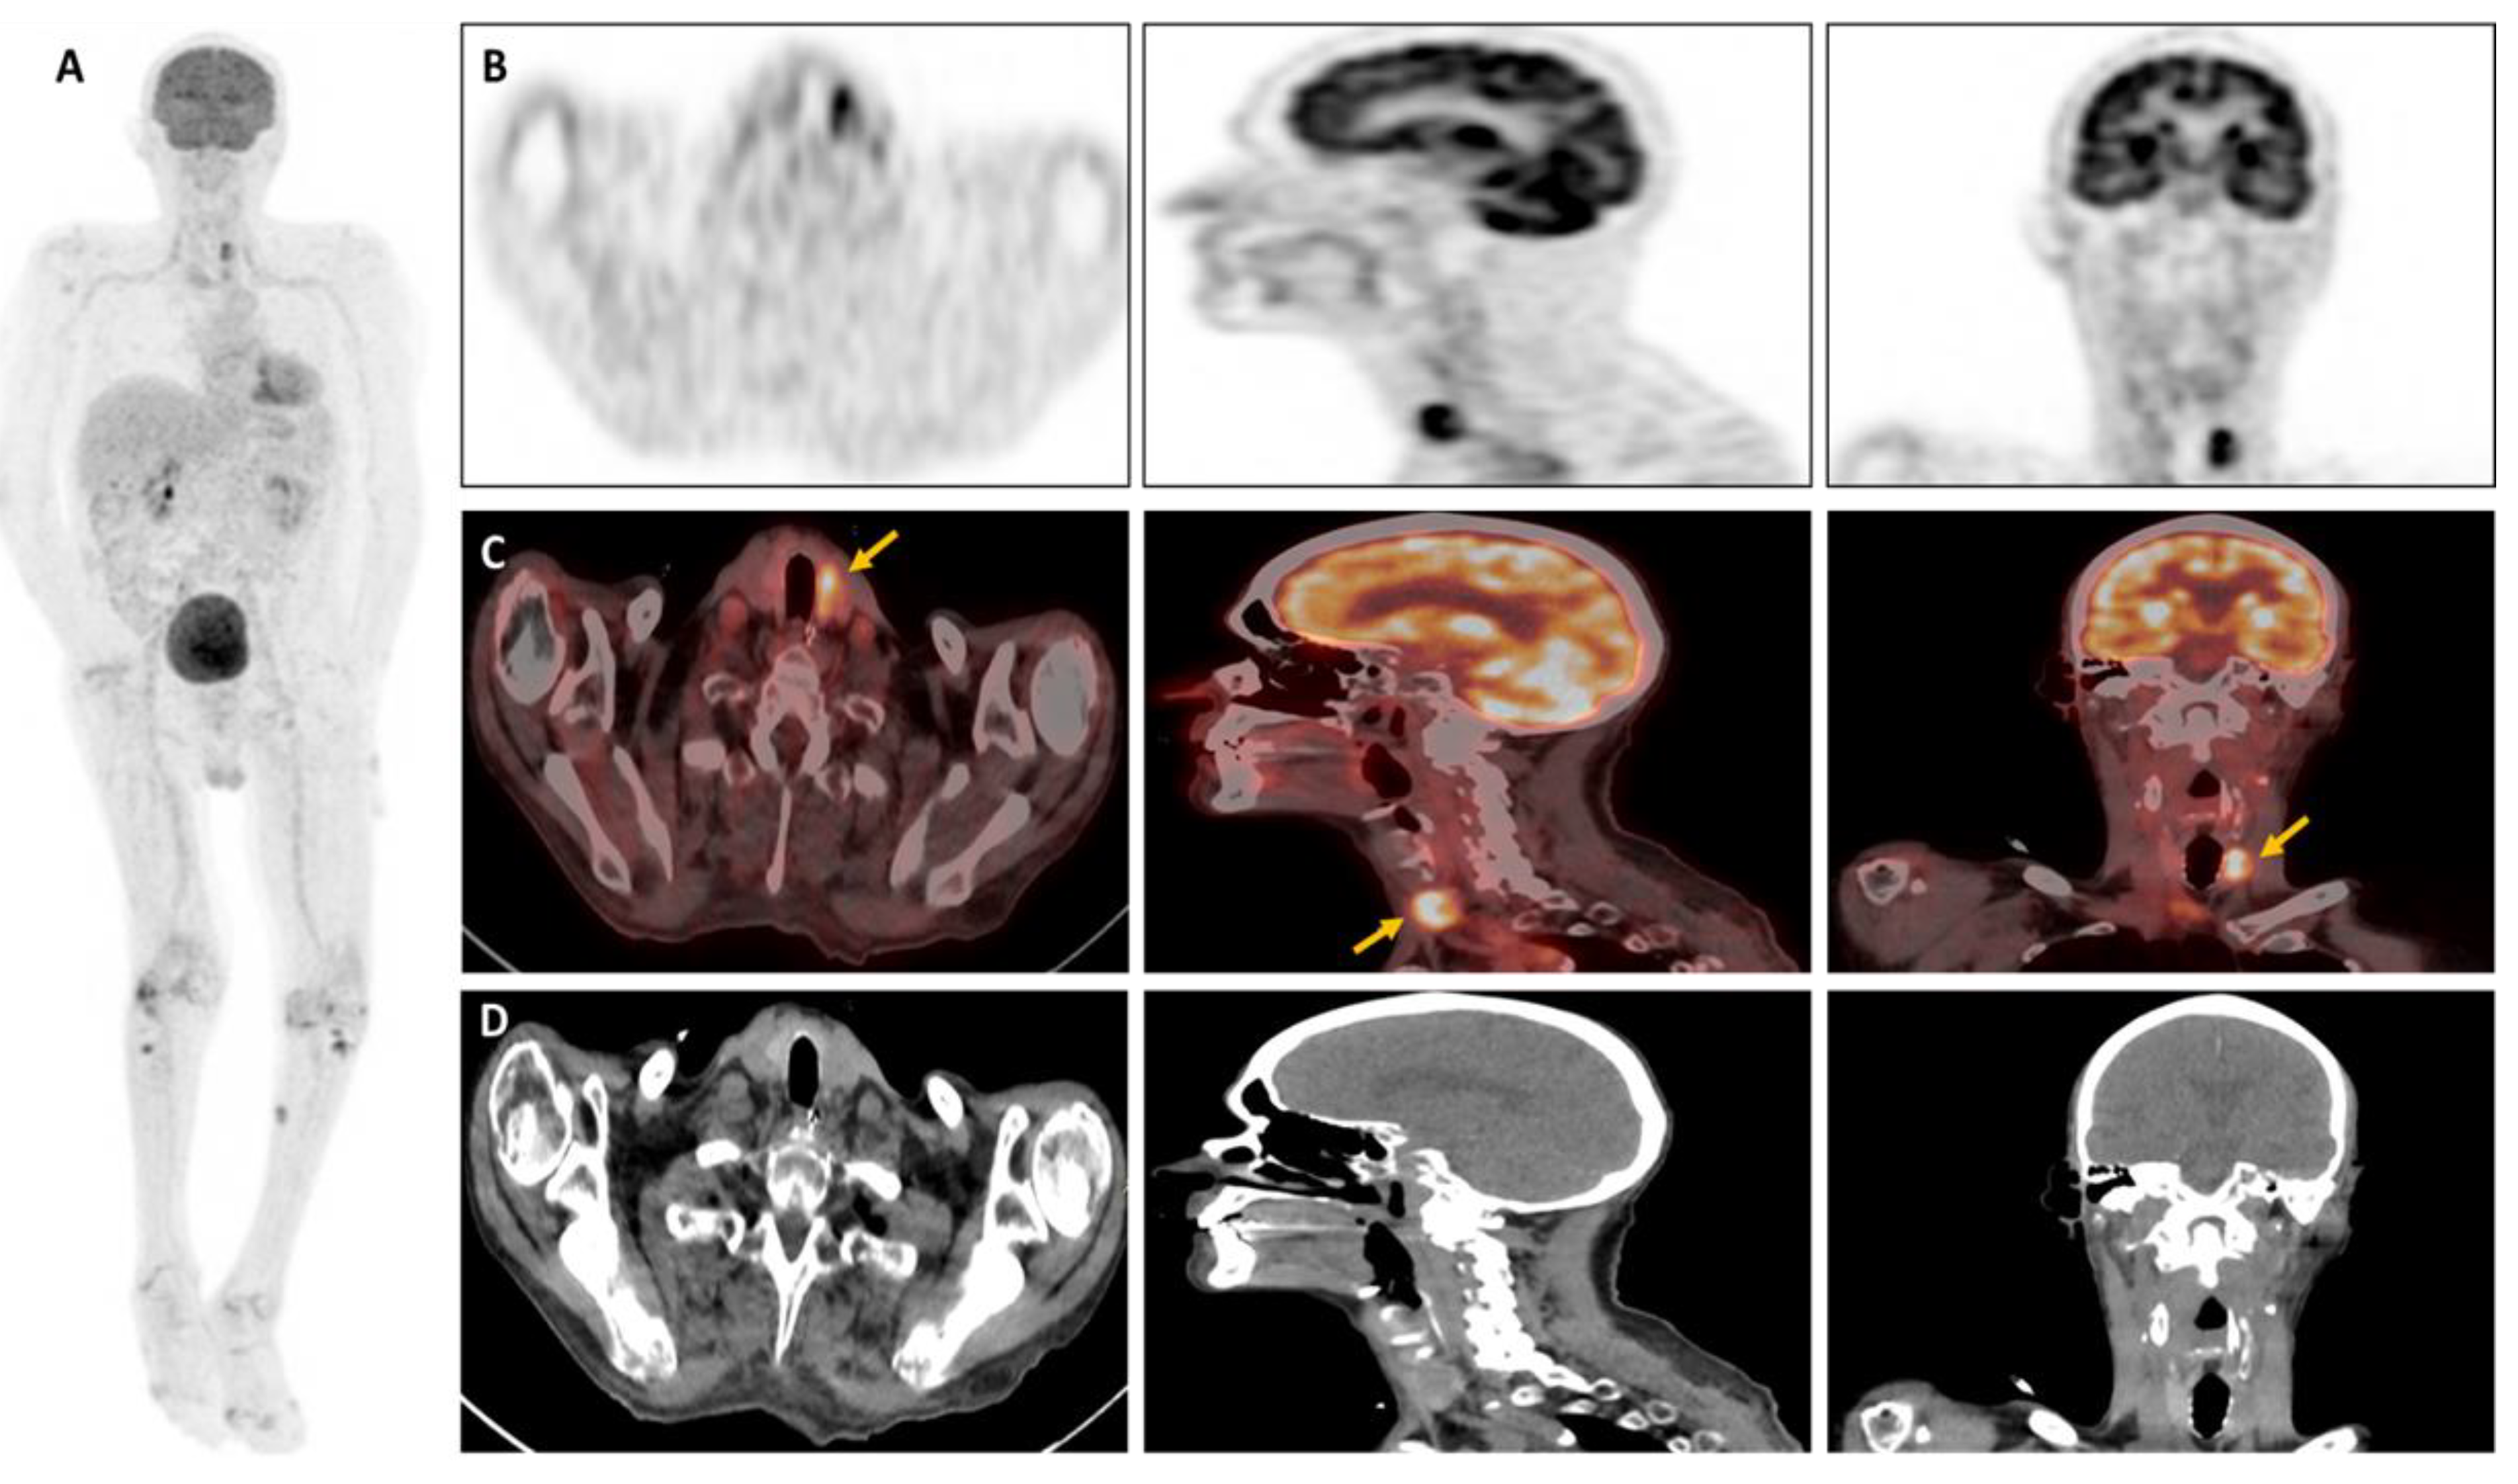

We report the case of a 71-year-old patient admitted to intensive care with severe abdominal-onset sepsis treated with broad-spectrum antibiotics. The patient had undergone liver transplantation for a moderately differentiated hepatocarcinoma operated on more than 1 year previously. During the workup, and given his immunosuppression, an extensive bacteriological mapping was carried out (viral, bacterial, parasitic, fungal) which came back positive for Clostridium difficile. Antibiotic therapy was rapidly modulated in the light of our results, with a favourable clinical and biological outcome. In her follow-up, we noted the presence of an aspergillary antigen which came back positive late and was checked 2 times. A thoracic CT scan was performed and showed the presence of two pulmonary nodules in the upper left lobar with frosted glass and the lower right lobar (Figure 2A,B). A bronchoalveolar lavage (BAL) was achieved, confirming the presence of Aspergillus fumigatus the diagnosis of pulmonary aspergillosis. An 18F-FDG-PET-CT was ordered to assess the presence of any extra-pulmonary sites and revealed subcutaneous/muscular nodules and focal hypermetabolism in the left thyroid lobe (Figure 1). In light of the results, a thyroid work-up was carried out; the biological tests came back normal, and the thyroid ultrasound revealed an iso- and hypoechoic EU-TIRADS-5 macro-nodule of the left lobe measuring 18x12x23mm, with vascularization around the perimeter, which had been punctured (Figure 2C,D). Histological findings showed the presence of an aspergill filament within the lesion, confirming the diagnosis of invasive thyroid aspergillosis (Figure 3). Aspergillosis is a prevalent fungal infection caused by inhaling spores (named conidia) of the mould Aspergillus [1]. These are generally contained in soils, plants, and decaying organic matter, but also in the air and indoor environments. Over 200 species of Aspergillus are currently thought to have been described, of which only around 10% are pathogenic to humans [2]. The genus Aspergillus comprises several hundred species, of which Aspergillus fumigatus remains the most common pathogenic agent, responsible for approximately 90% of cases of Aspergillus disease, followed by Aspergillus flavus, Niger, Terreus and Nidulans [3]. In general, Aspergillosis is fairly widespread. Depending on the patient’s immunity, they can lead to various forms of clinical presentation, ranging from an isolated form to multi-organ involvement [5]. The most severe forms, known as “invasive”, are usually seen in immunocompromised patients due to HIV infection, oncological conditions, intensive chemotherapy, immunosuppressive drug therapy, post-transplant conditions, or other chronic diseases, and may be associated with high mortality rates and life-threatening illness [6]. It is therefore crucial to assess both the extent of the disease and the effectiveness of treatment, with several diagnostic strategies currently available. The cornerstone of IA diagnosis is biopsy-based fungal culture, supplemented by other biomarker tests such as galactomannan in serum and bronchoalveolar lavage fluid (BAL) [7]. Conventional CT imaging is generally useful in diagnostic management, but radiological features of aspergillosis are not specific, and the CT finding termed the “halo-signal” is a sign that may not always be clearly detectable [8].

Figure 1. 18F-FDG-PET/CT of the patient: (A) Maximum Intensity Projection (MIP) of the entire body. (B) Maximum Intensity Projection (MIP) of the head section passes at the level of the thyroid compartment. (C) fused PET/CT images, (D) CT-images.